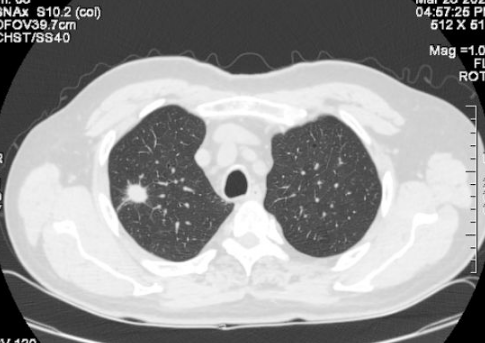

近年来,肺结节的发病率越来越高。我们经常可以看到或听到身边的亲友,体检时发现肺结节。造成这种情况的原因,一方面是现代人生活节奏快、工作压力大、生活习惯差、空气污染等,导致肺结节的发病率较以前有所增加。另一个方面是,过去在例行体检中,通过胸部X光片来确定肺部的状况。

但是X线对软组织的分辨率不是很高,小于一厘米的结节很难发现。现在,越来越多的人在体检时选择胸部CT检查。这样,随着医学影像诊断技术的进步,两到三毫米的肺结节也能被发现和检测到。因此,总的来说,肺结节的发现率越来越高。

正常人群肺结节检出率因地区而异。根据目前的情况,最低可能是20%,最高可能是40%-50%,甚至70%,这可能与参与调查的正常人群有所不同。年龄不一样。 30-70岁的正常人可能会发现70%的人有肺结节,一般在20%-40%左右。肺结节发生率高,但恶性程度低。有可能90%以上的肺结节是良性结节,最终诊断为恶性肿瘤的约有5%左右。

肺结节的发病率虽然高,但主要是由非肿瘤因素引起的。由于肺癌是最常见的癌症,大家对肺癌的关注度也越来越高。肺癌的监测和筛查方法通常是胸部CT。胸部CT做的越多,肺结节的发生率和检出率就会增加。由于肺癌仅占其中的5%左右,因此肺结节大可不必过于紧张。 .必要的检查、观察和随访更为重要。做到早筛查、早发现、早治疗。大多数肺癌患者都能取得较好的治疗效果。